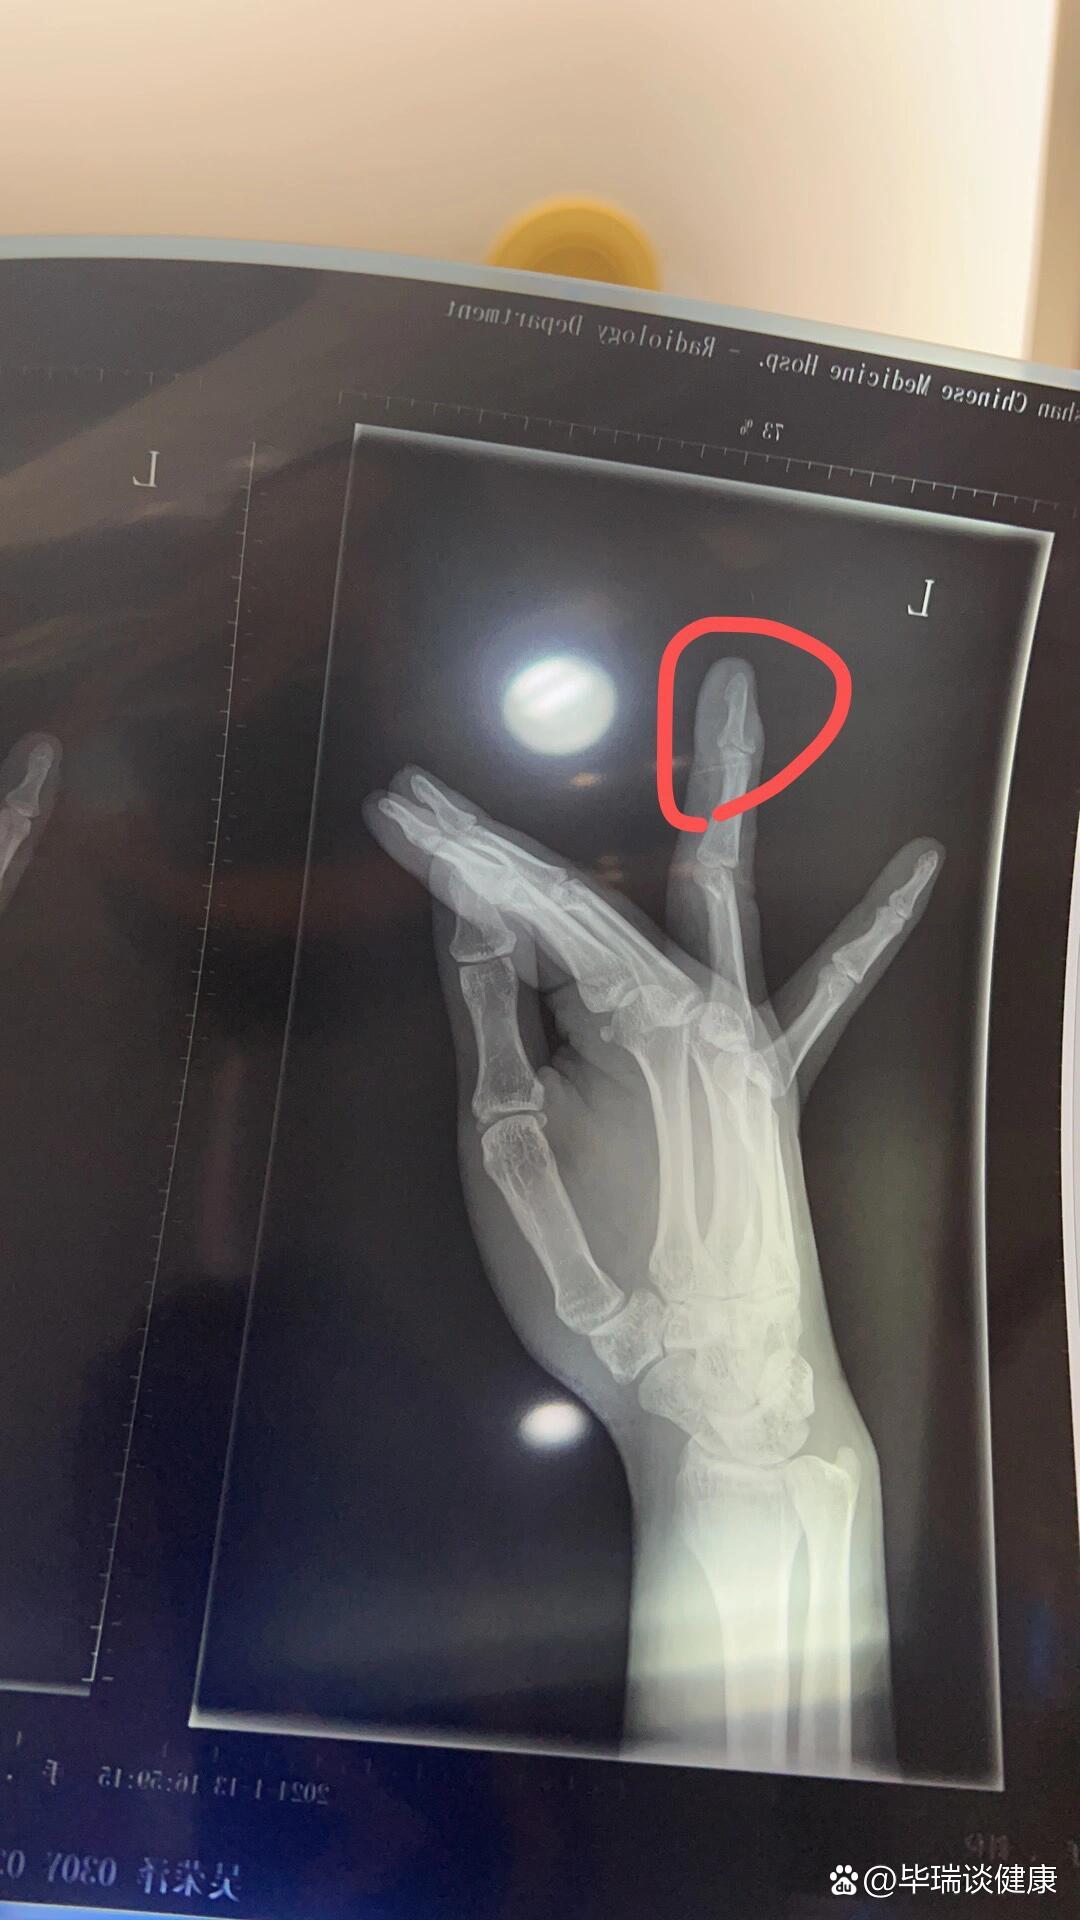

右手环指近节指骨骨折

右手中指第一节指骨近端骨折